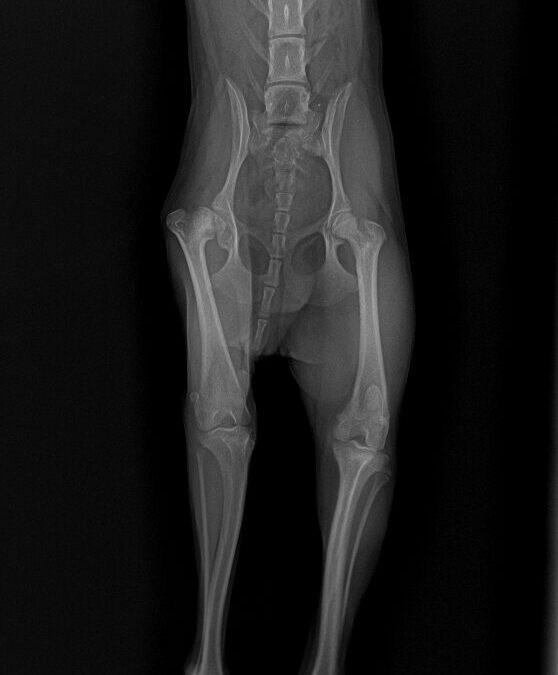

症例は 8ヶ月のヨークシャーテリアで1ヶ月前から片足を着いていないとの主訴で来院しました。

レントゲンを取ると右の股関節(左側)が変形していることが分かります。大腿骨頭が壊死している影響で痛みが出ている可能性が高い状態でした。左右の筋肉量を比較すると右足(左側)の筋肉が萎縮しており、長期間右後肢を使っていなかったことが分かります。

手術では大腿骨頭を切除します。骨盤の骨に当たらないかどうかを確認して、当たる部分は削り取っていきます。一般的に大腿骨頭切除を行うと、その後に股関節が不安定になり、大腿骨が背側にずれていく現象が見られることがありますが、術中に対処を行うことで当院ではその発生率を下げております。